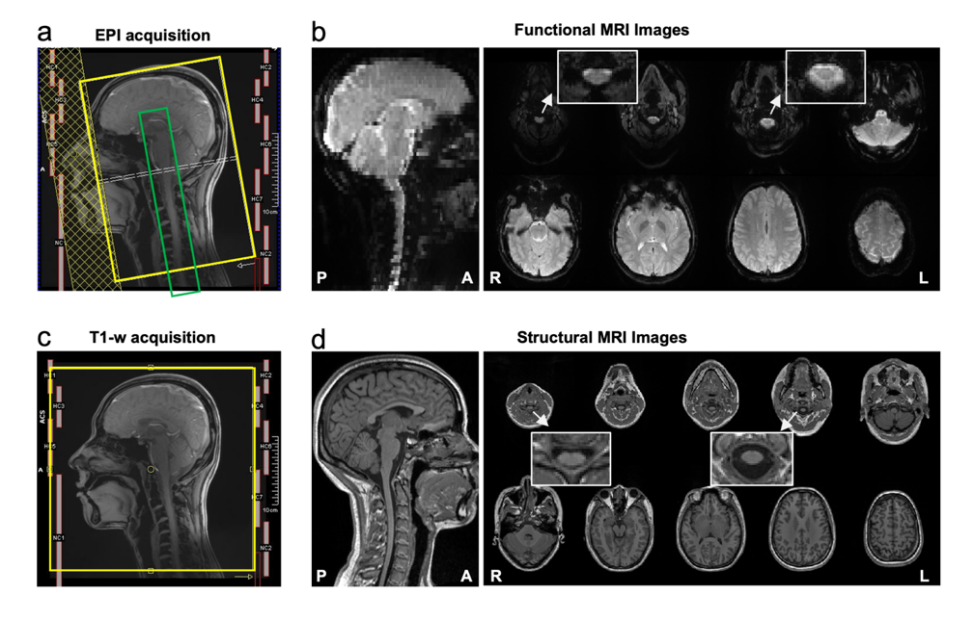

CoSpine成像方案基于西門子 3T Prisma 磁共振系統,實現了覆蓋大腦、腦干、小腦及頸段脊髓的單視野同步采集(見圖1)。該方案融合多頻帶并行采集與并行重建算法,在保持1.5毫米高空間分辨率的同時,大幅提升了時間采樣效率與圖像質量。這一成像策略使皮層—腦干—脊髓神經信號得以在一次掃描中連續獲取,為系統性研究腦–脊髓功能交互研究奠定了方法學基礎。

圖1. CoSpine功能與結構成像的采集方案及示意圖